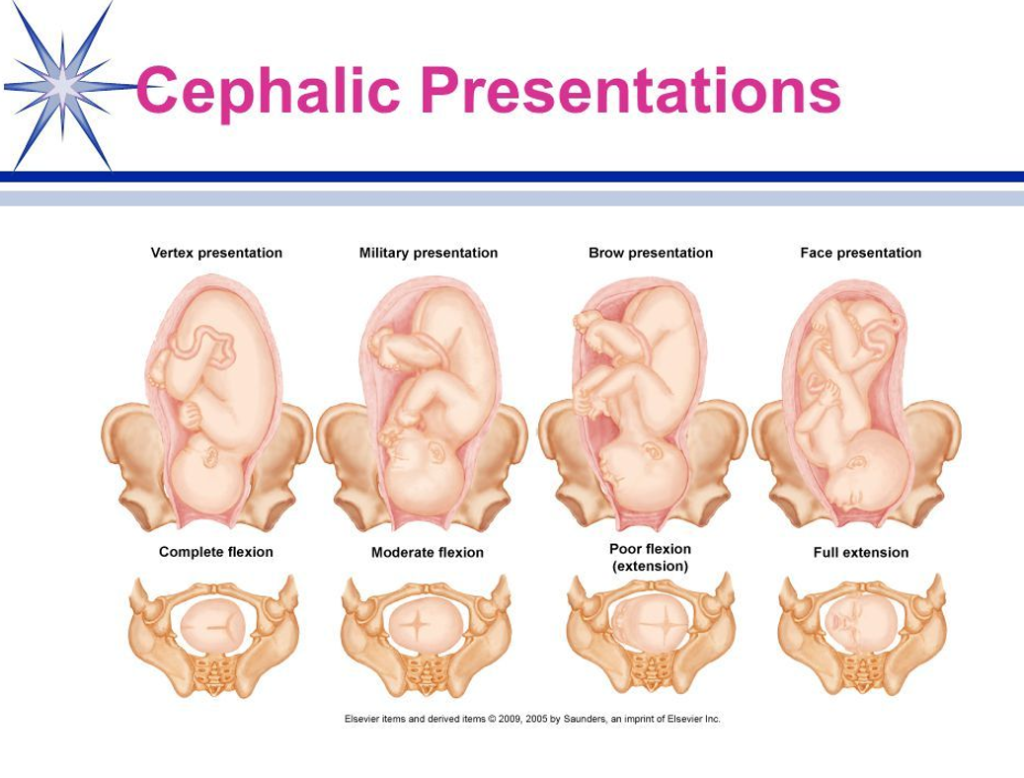

Votre bébé se positionne en vue de l’accouchement en Présentation céphalique habituelle.

Le plus souvent, quelques semaines avant la naissance, le bébé se positionne naturellement pour sa venue au monde : tête en bas et bien fléchie. Cette présentation céphalique permet, le plus souvent, un accouchement normal, par voie basse.

La césarienne peut être programmée à l’avance, par exemple si :

- Le bébé se présente de manière particulière